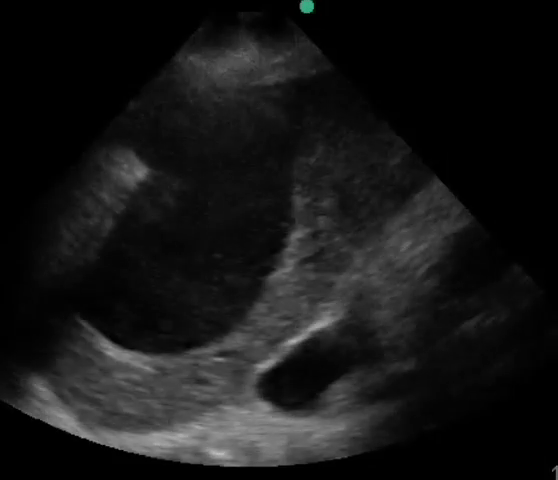

Point-of-care sonography was performed in order to assess volume status and the following representative image was obtained